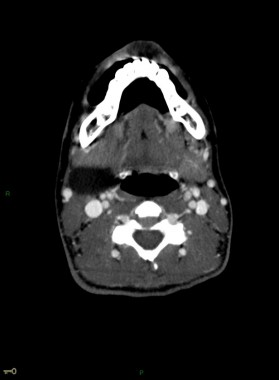

Kyste du 2ème arc branchial (type 2)